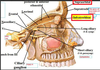

Where is the Supraorbital foramen/notch?

What structures can be found there

the supraorbital nerve and vessels are located here.

Where is the infraorbital foramen/notch?

What structures are found here?

the infraoribal nerve and vessels are found here.

Where are the infra and supratrochlear foramen located?

What structures are found here?

supratrochlear nerve and vessels, as well as infratrochlear nerve and vessels.

Where is the zygomaticofacial foramen?

what is located here?

zygomaticofacial nerves and vessels.